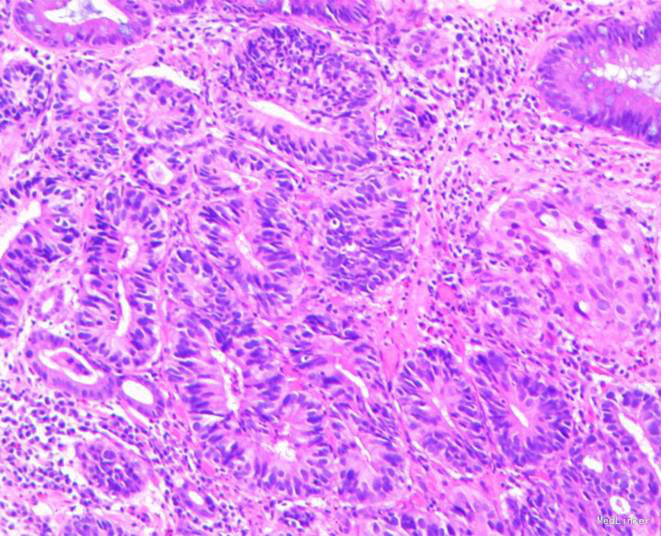

患者,男性,69岁,间歇性中上腹隐痛1月,加剧1周来我院门诊就诊,胃镜检查:见胃窦前壁处可见一1.5*2.0cm粘膜隆起,表面粗糙,见图1,胃镜诊断:胃窦粘膜隆起(性质待病理),慢性浅表性胃窦炎伴胆汁反流,10月26日门诊病理:胃窦:慢性萎缩性胃炎,急性活动,伴部分腺体中重度不典型增生,局灶重度不典型增生。于2015年10月28日入院。

随访:出院后2周,电话随访患者,一般情况良好,无不适主诉。 讨论:该患者胃镜见一胃窦前壁粘膜隆起,表面粘膜粗糙,病理示:慢性萎缩性胃炎,伴部分腺体中重度不典型增生,局灶重度不典型增生,超声胃镜病灶未突破粘膜下层,有胃ESD手术指征,故行全麻下胃ESD术。术后病理:胃窦前壁肿瘤:腺上皮高级别上皮同瘤,部分癌变,病变大小1.5*1.1*0.3cm,基底及切缘未见癌。说明手术成功,切缘及基底均无肿瘤侵及。对于早癌患者我们完全可以通过采用ESD方法治愈患者,胃镜下切除早癌较腹腔镜创伤更小。我和患者解释时是这样说的:腹腔镜是微创,而我们内镜下ESD则是微微创。